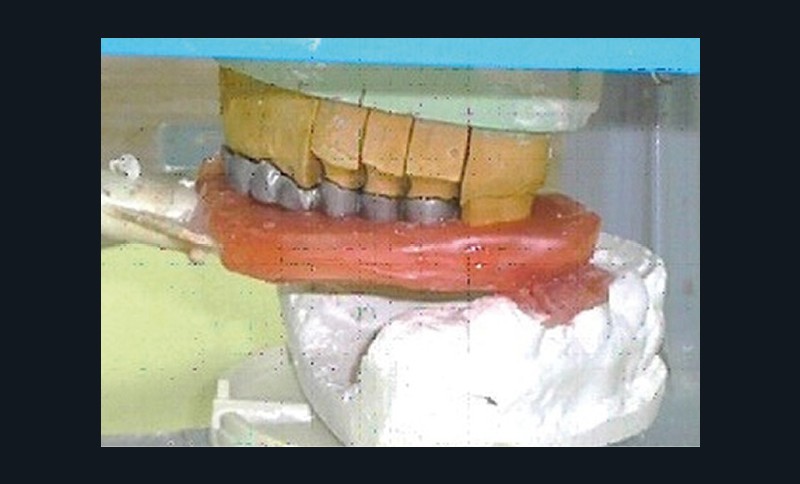

Analyse sur articulateur : les moulages d’étude transférés par le biais d’un arc facial sur articulateur semi-adaptable à la bonne dimension verticale d’occlusion sont analysés.

- Cire de diagnostic : le wax-up, ou cire de diagnostic, a été effectué (fig. 7). Ce guide référentiel thérapeutique permet de concrétiser le projet prothétique d’un point de vue esthétique et fonctionnel ; il constitue un outil indispensable de communication à la triade patient/praticien/prothésiste [10-12].

Confection de la prothèse d’usage : la prothèse transitoire est restée deux mois en bouche, jusqu’à l’intégration fonctionnelle et la satisfaction esthétique de la patiente [13,14]. Puis, la prothèse d’usage est confectionnée, en commençant par la réalisation de l’armature métallique au laboratoire (fig. 13a-h).